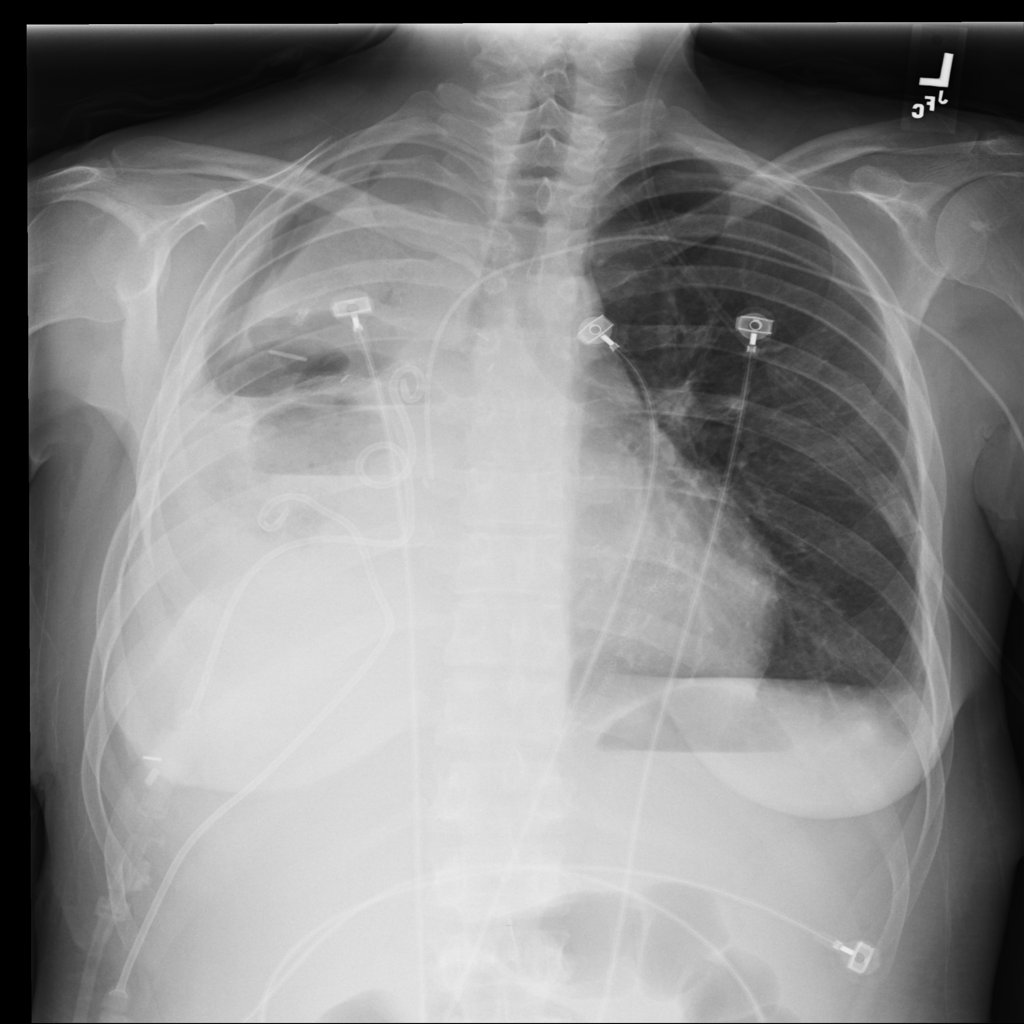

Pleural Effusion representative X-ray

Reference image: PAT-CF38 · IMG-012 · Bounding-box highlight from source annotation where available.

• On chest X-ray, pleural effusion may appear as blunting of the costophrenic angle, a meniscus-shaped opacity, layering fluid, or broader dependent hazy opacity depending on patient position and volume

• Radiologists look for costophrenic angle blunting, meniscus sign, layering fluid, associated atelectatic change, and whether the effusion is unilateral, bilateral, or large enough to shift adjacent structures